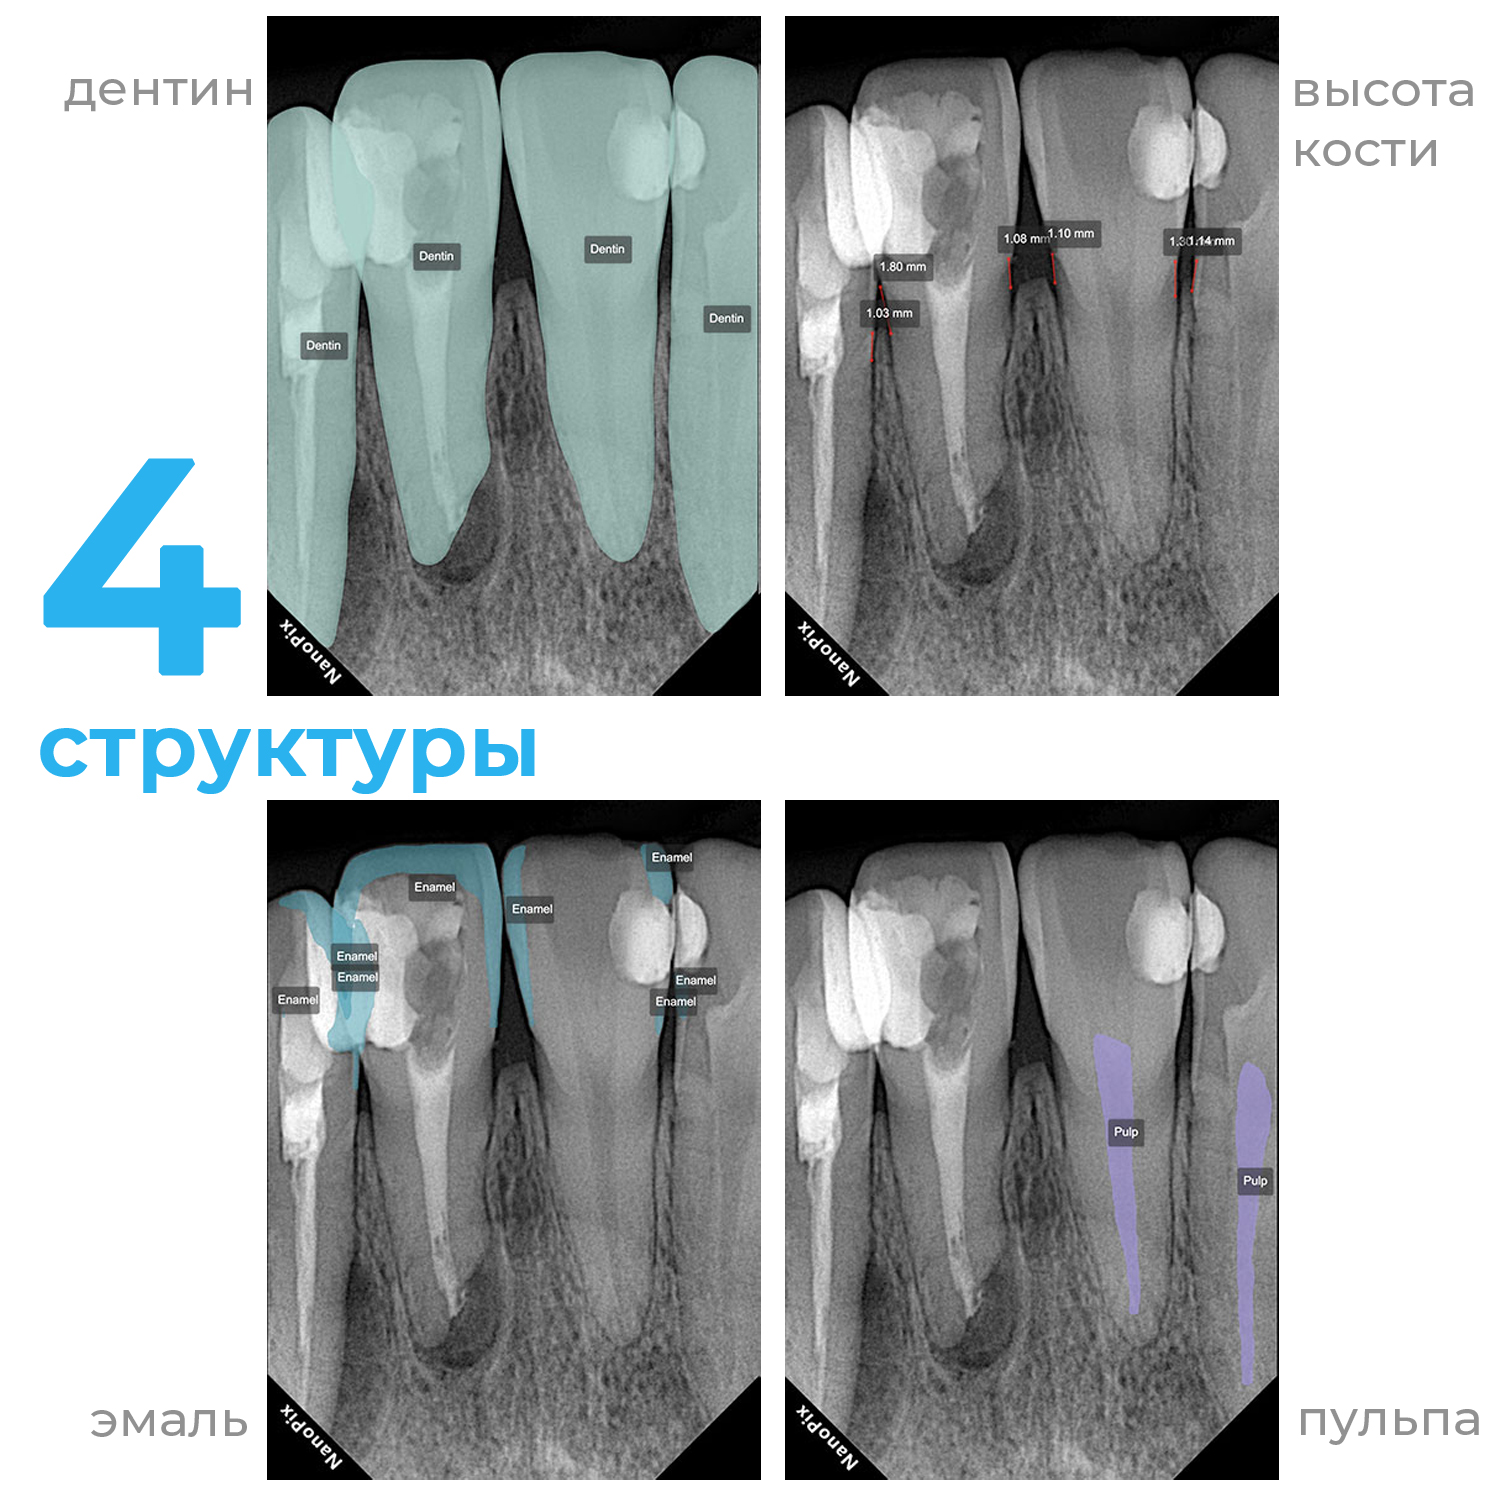

Прибор оснащён высокочувствительным сенсором, с помощью которого устройство фиксирует и передаёт изображение в цифровом виде на компьютер. Принцип работы заключается в следующем: цифровой радиовизиограф размещается в ротовой полости пациента за зубами. С щёчной стороны дентальный рентгеновский аппарат выпускает в направлении радиовизиографа рентгеновские лучи. Лучи, проходя через ткани зуба, фиксируются на радиовизиографе, и полученная информация отображается на экране компьютера. Уникальная технология искусственного интеллекта Nano AI распознаёт зубные патологии, выделяя их цветом и предлагая возможные способы лечения.